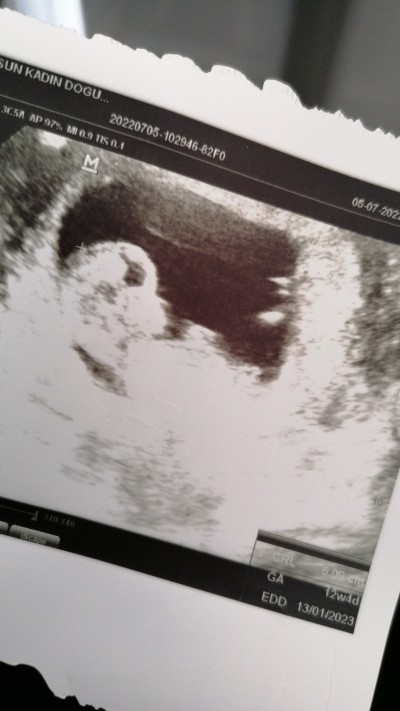

Merhaba kızlar ikinci gebeliğime hamileyim 12+4 haftalık. Bugün doktoruma cinsiyeti belli mi dedim bi tık kıza benziyor ama tam net belli değil dedi.

image